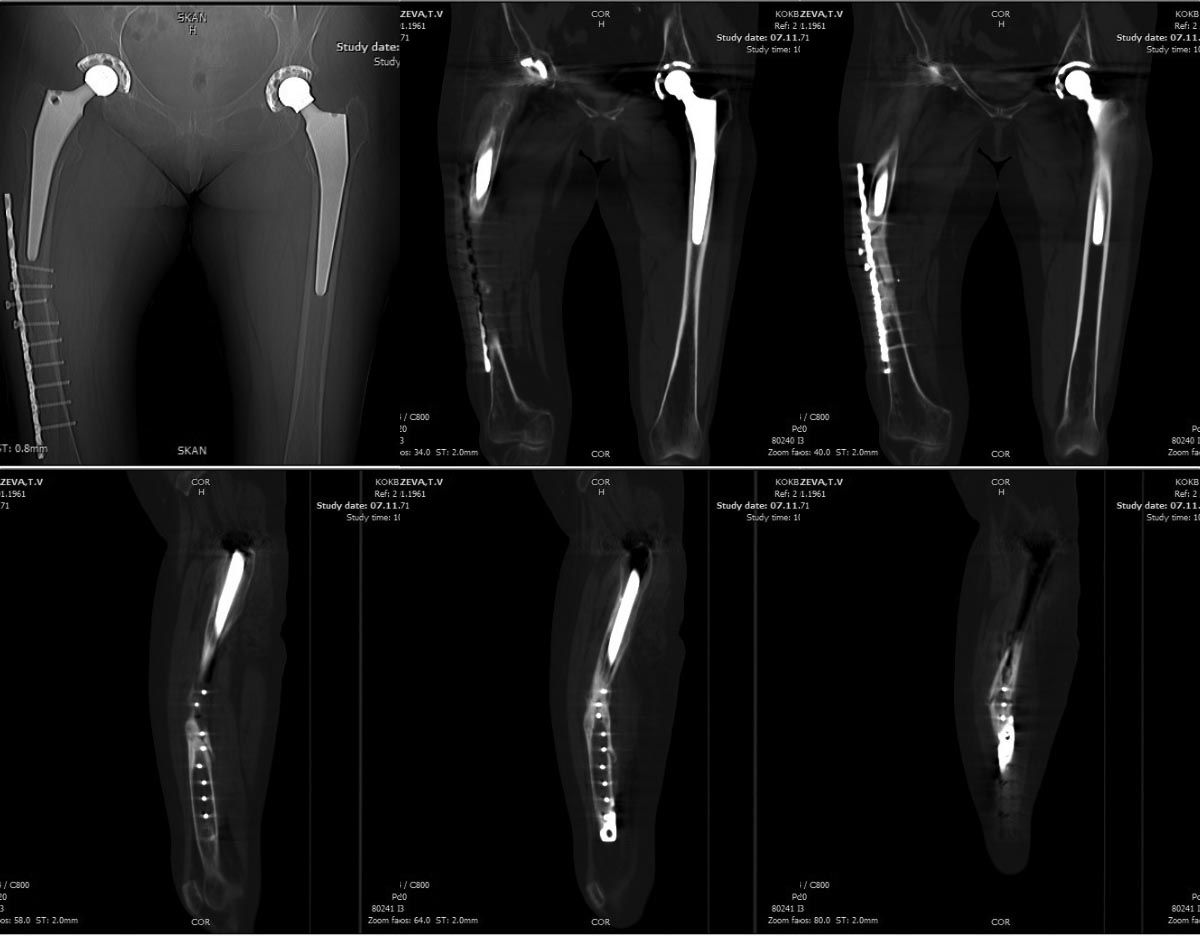

[Ortho] Перипротезный перелом

п≤п╪я▐     : collage.jpg